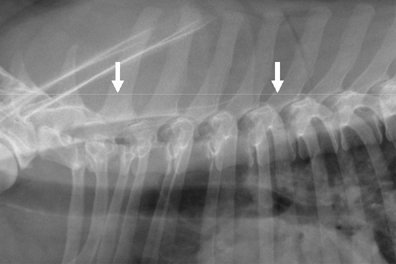

Analysis of the radiograms field sizes with pre- and post-processing collimation Streszczenie Wstęp: Kolimacja jest to ograniczanie wiązki promieniowania entgenowskiego do obszaru badanej części ciała, pozwalające ochronić pozostałe tkanki przed zbędnym narażeniem. Definicja ta dotyczy kolimacji przedekspozycyjnej, czyli przed wykonaniem emisji promieniowania, z wykorzystaniem symulacji świetlnej. Cel: Celem badania była analiza pól radiogramów z kolimacją…